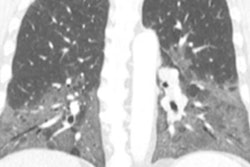

Chest radiograph reported as normal. Note the diffuse ground-glass shadowing in all zones. Images courtesy of Dr. Patrick Liu-Shiu-Cheong, Dr. Owen Dempsey, and BMJ Case Reports 2019."Our patient's CXR [chest x-ray] report was initially reported as normal (although we disagreed)," the authors wrote. "He subsequently had a CT pulmonary angiogram with high-resolution reconstruction (to exclude pulmonary thromboembolic as well as interstitial lung disease), reported as showing a ground glass, mosaic pattern in both lungs, with borderline enlarged hilar nodes, presumed reactive."

CT scan shows mosaic pattern; middle zones axial view.